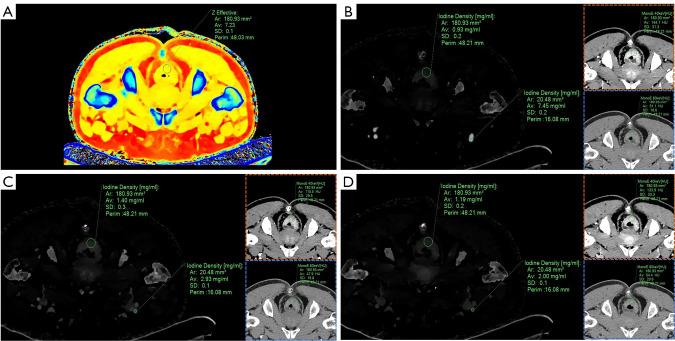

Consecutive patients suspected of having CRC and with a clinical indication for enhanced CT from April 2021 to July 2022 at a single institution were prospectively enrolled to undertake spectral CT scanning. The spectral features were extracted by two reviewers and intraclass correlation coefficient (ICC) was used for interobserver agreement evaluation. A total of 16 spectral parameters, including unenhanced effective atomic number, triphasic iodine concentrations (ICs)/normalized ICs (NICs)-/1/NIC-/spectral curve slopes (λ-), two arterial enhancement fractions (AEFs), and venous enhancement fraction (VEF), were determined for analysis. Patients with and without VEDM after surgery were matched using propensity score matching (PSM). The diagnostic performance was assessed using the area under the curve (AUC). Models of multiple modalities were generated.

In total, 222 patients were included (141 males, age range, 32-83 years) and 13 patients developed VEDM. Interobserver agreement ranged from good to excellent (ICC, 0.773-0.964). A total of three spectral parameters (VEF, λ-, and 1/NIC-) exhibited significant discriminatory ability (P<0.05) in predicting VEDM, with AUCs of 0.822 [95% confidence interval (CI): 0.667-0.926], 0.738 (95% CI: 0.573-0.866), and 0.713 (95% CI: 0.546-0.846) and optimal cutoff points of 67.16%, 2.46, and 2.44, respectively. The performance of these spectral parameters was validated in the entire cohort; the combined spectral model showed comparable efficiency to the combined clinical model [AUC, 0.771 (95% CI: 0.622-0.919) 0.779 (95% CI: 0.663-0.894), P>0.05]; the clinical-spectral model achieved further improved AUC of 0.887 (95% CI: 0.812-0.962), which was significantly higher than the combined clinical model (P=0.015), yet not superior to the combined spectral model (P=0.078).